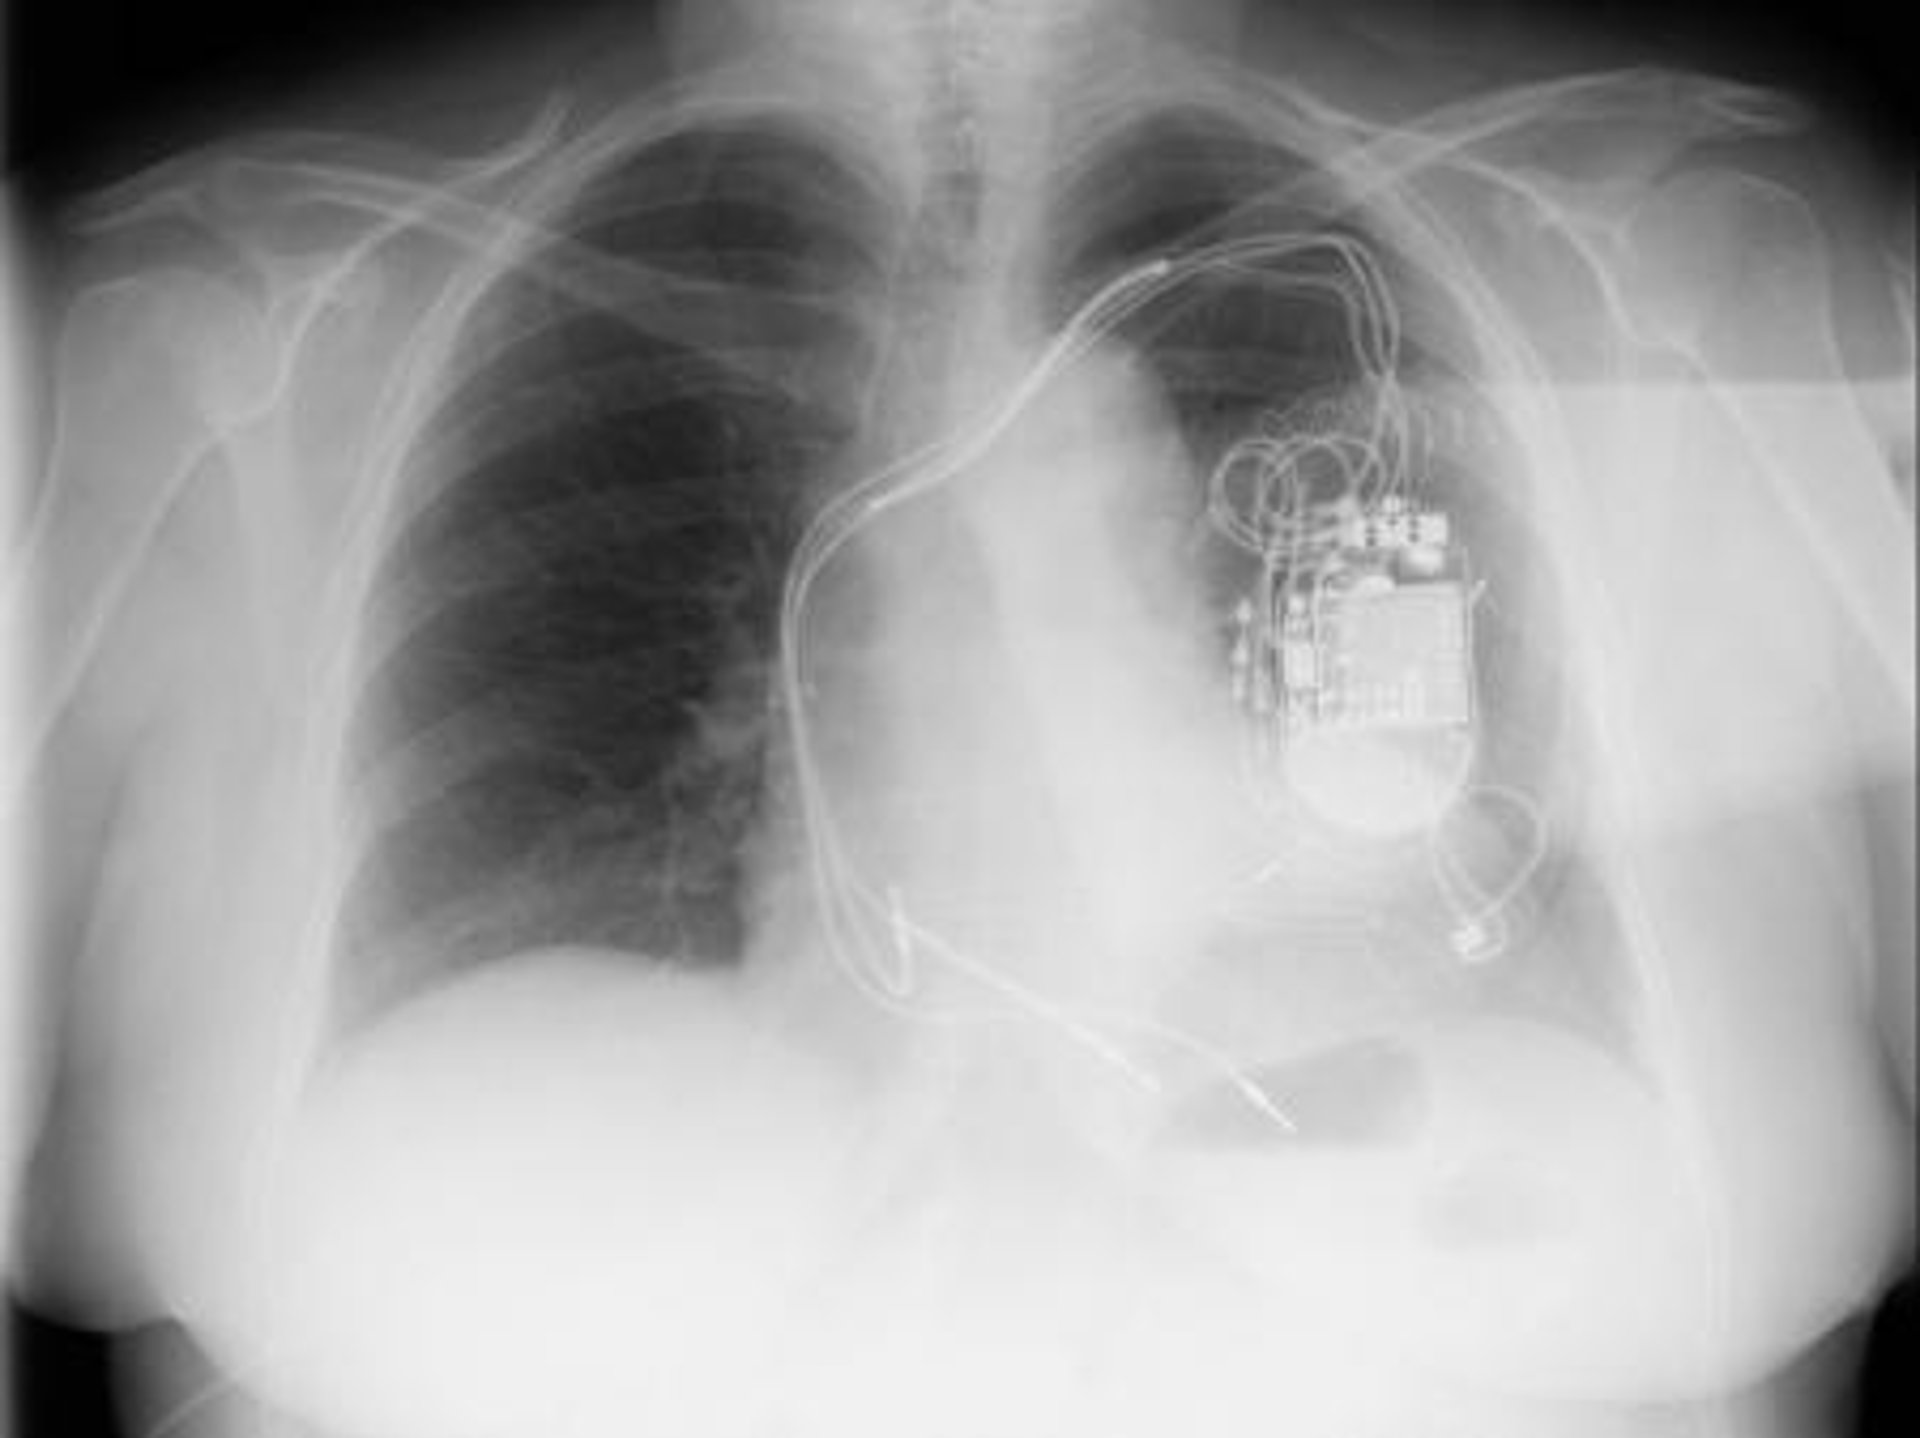

Consiste básicamente en la colocación de un generador -marcapasos o desfibrilador, según los casos-, que contiene la fuente de energía y el software para regular su funcionamiento, y tres electrodos, uno en cada ventrículo y otro en la aurícula derecha, para que los dos ventrículos se contraigan de manera simultánea y homogénea.

Habitualmente, el generador se coloca por debajo de la clavícula izquierda y los electrodos se introducen por la vena subclavia hasta su destino en la parte correspondiente del corazón. Con el procedimiento convencional, el electrodo del ventrículo izquierdo se implanta a través del sistema venoso situado en la parte externa del corazón, pero esta técnica falla en un 10 por ciento de los casos por problemas de acceso, generalmente porque el paciente tiene un sistema venoso que anatómicamente no es adecuado para el implante.

La nueva técnica evita este problema introduciendo el electrodo del ventrículo izquierdo por la vena femoral, situada en la pierna, hasta la aurícula derecha, desde donde se pasa a las cavidades izquierdas haciendo una punción en la pared que separa ambas aurículas, y luego se captura para conducirlo a través de la vena subclavia y conectarlo al generador.